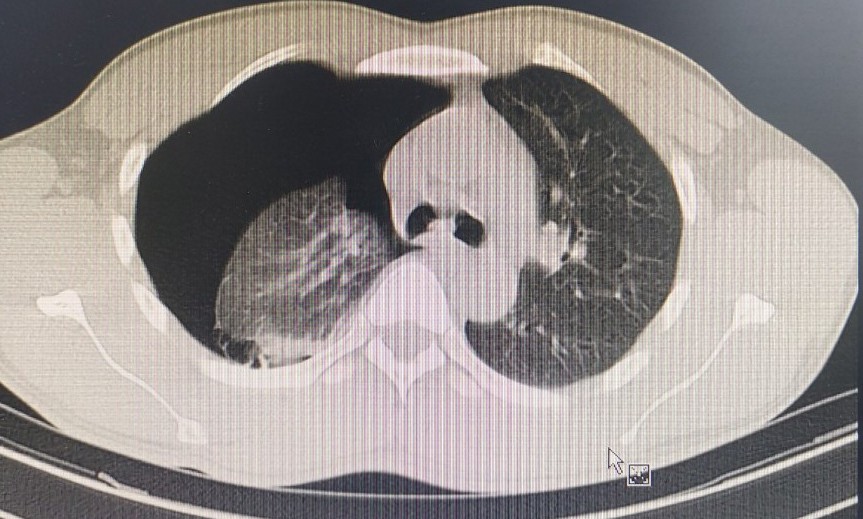

Kết quả chụp phim X-quang phổi bệnh nhân có dịch, có khí. Các bác sĩ chẩn đoán anh bị tràn khí màng phổi tự phát. Đây là bệnh thường gặp, có thể ảnh hưởng nghiêm trọng sức khỏe cũng như nguy hiểm tính mạng, nếu không xử lý đúng cách và can thiệp kịp thời.

Bệnh nhân được chỉ định phẫu thuật dẫn lưu màng phổi cấp cứu, mổ khâu kén khí và cầm máu, làm sạch khoang màng phổi. Bác sĩ áp dụng kỹ thuật phẫu thuật cắt kén khí qua nội soi, giảm đau sau mổ, đường mổ rất nhỏ nên tính thẩm mỹ cao.

Nguyên nhân dẫn đến bệnh thường do vỡ các bóng khí ở đỉnh phổi. Cơ chế hình thành các bóng khí có thể do bẩm sinh hoặc do viêm tiểu phế quản tận. Bệnh thường gặp ở người cao, gầy vì cơ địa này áp lực đỉnh phổi thấp hơn, dễ gây vỡ các bóng khí. Khoảng 30% trường hợp tràn khí màng phổi tự phát nguyên phát bị tái phát sau điều trị dẫn lưu màng phổi đơn thuần.